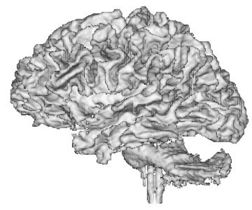

| + | {| | ||

| + | |+ '''Fig 2. EM Segmentation: 3D Rendered Segmentations (1993)''' | ||

| + | |valign="top"|[[Image:four.jpg|thumb|252px|3D view of segmented white matter surface from thresholding]] | ||

| + | |valign="top"|[[Image:five.jpg|thumb|252px|3D view of segmented white matter surface from EM]] | ||

| + | |} | ||